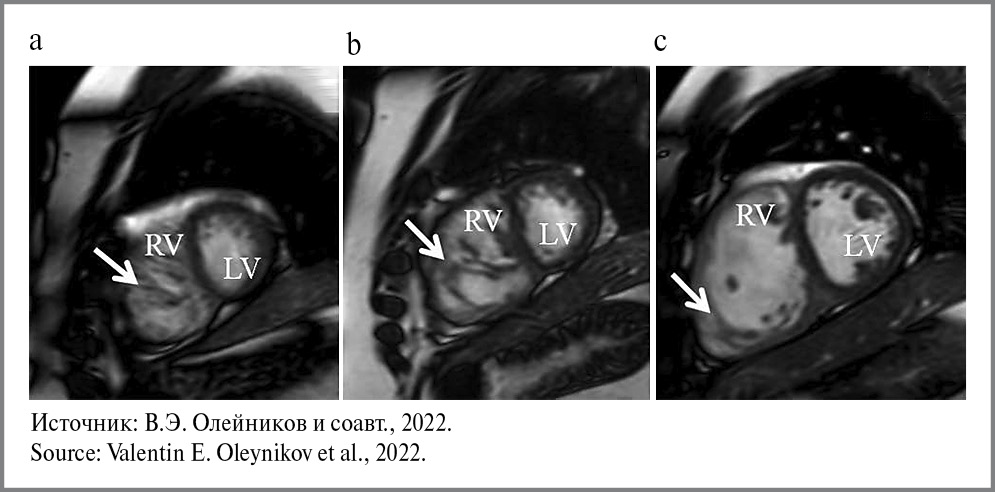

Таким образом, в профессиональном сообществе вопрос об изолированном поражении ПЖ остается спорным, и до настоящего времени не предложено однозначных критериев дифференциальной диагностики повышенной трабекулярности ПЖ [6]. Для разрешения существующих противоречий предлагаются косвенные критерии патологического характера повышенной трабекулярности ПЖ. В частности, указывается, что признаком патологической некомпактности миокарда ПЖ необходимо признать его дилатацию [11, 33]. Отмечается важность распространения трабекулярности по латеральной стенке ПЖ с поражением трикуспидального клапана в тяжелых случаях [32]. Значимым дифференциально-диагностическим показателем является наличие выраженных трабекул, которые, в отличие от анатомических вариаций, проходят от свободной стенки к межжелудочковой перегородке (рис. 1, 2) [1, 34]. В дополнение предлагается гистологическая шкала диагностики, при применении которой повышенная трабекулярность ПЖ признается патологической при толщине некомпактного миокарда >75% [5].

Рис. 1. а – МРТ сердца, четырехкамерная проекция. Стрелка – граница некомпактного миокарда в апикальном отделе ПЖ; b – МРТ сердца, проекция выводного тракта ЛЖ. Стрелка – граница некомпактного миокарда в базальных отделах ПЖ. / Fig. 1. a – magnetic resonance imaging (MRI) of the heart, four-chamber projection. The arrow is the border of the non-compact myocardium in the apical pancreas; b – MRI of the heart, projection of the left ventricular outflow tract. The arrow is the border of the non-compacted myocardium in the basal sections of the right ventricle.

Рис. 2. МРТ сердца, проекции по короткой оси: а – апикальные отделы; b – средние отделы; c – базальные отделы. Выраженность некомпактного миокарда в разных отделах ПЖ. / Fig. 2. MRI of the heart, projections along the short axis: a – apical sections; b – middle sections; c – basal sections. The severity of non-compact myocardium in different parts of the right ventricle.